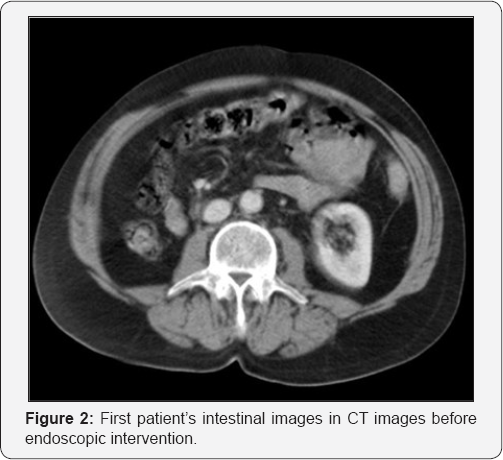

A 75-year-old male patient presented with the complaints of abdominal pain, nausea and vomiting for two days was evaluated in the emergency department. Stool discharge was present. We learned from the history that he had undergone gastric surgery due to ulcer 25 years ago and coronary by-pass surgery 4 years ago. Physical examination revealed midline operation scar above the belly and epigastric distention and tenderness. No other pathologic finding was detected in other abdominal quadrants. The patient's leukocytosis value was 13000/mm3. No other pathological finding was found. No pathology was visualized in the standing direct abdominal x-ray. The urgent or emergent abdominal computed tomography revealed a phytobezoar-like appearance causing obstruction at the gastric outlet (Figure 1 & 2).

In the urgent endoscopic examination of the patient, the stomach was visualized to be full, showing an obstruction along with phytobezoar at the outlet (Figure 3). The phytobezoar was broken down with endoscopic hook and its transition to the duodenum was visualized (Figure 4). However, as a result of distention finding in the patient whose vomiting complaint have restarted during the follow-up, abdominal CT was repeated and phytobezoar causing obstruction at the ileum was visualized (Figure 5 & 6). An emergent operation was planned for the patient, and prior to the operation, prophylactic 1 g of cephazolin and 500 mg of metronidazole were intravenously administered and the patient was taken into emergent operation and underwent enterotomy after diagnostic laparotomy, and phytobezoar was removed (Figure 7 & 8). The patient who did not have any complaint or complication postoperatively, was discharged.

Clinically, patients present with obstruction findings, such as abdominal distention, abdominal pain, nausea and vomiting [1]. Direct x-rays, the firstline diagnostic techniques, may provide visualization of ileus findings, such as air-fluid levelings, as well as free air in cases of perforation. However, they are not sufficient to reveal the etiologic cause [1]. The abdominal CT is an important diagnostic tool with a sensitivity rate of 90% and a specificity rate of 96%. Well-demarcated intra-luminal mass with air bubbles, along with dilated intestinal loops and collapsed loops following mass can be visualized in CT [7]. In our first case, a gastric phytobezoar that migrated after the endoscopy was visualized in the jejunal loops in the tomographic images (Figures 1-4). Whereas in our second case, bezoar causing obstruction in the ileum was visualized (Figure 5).